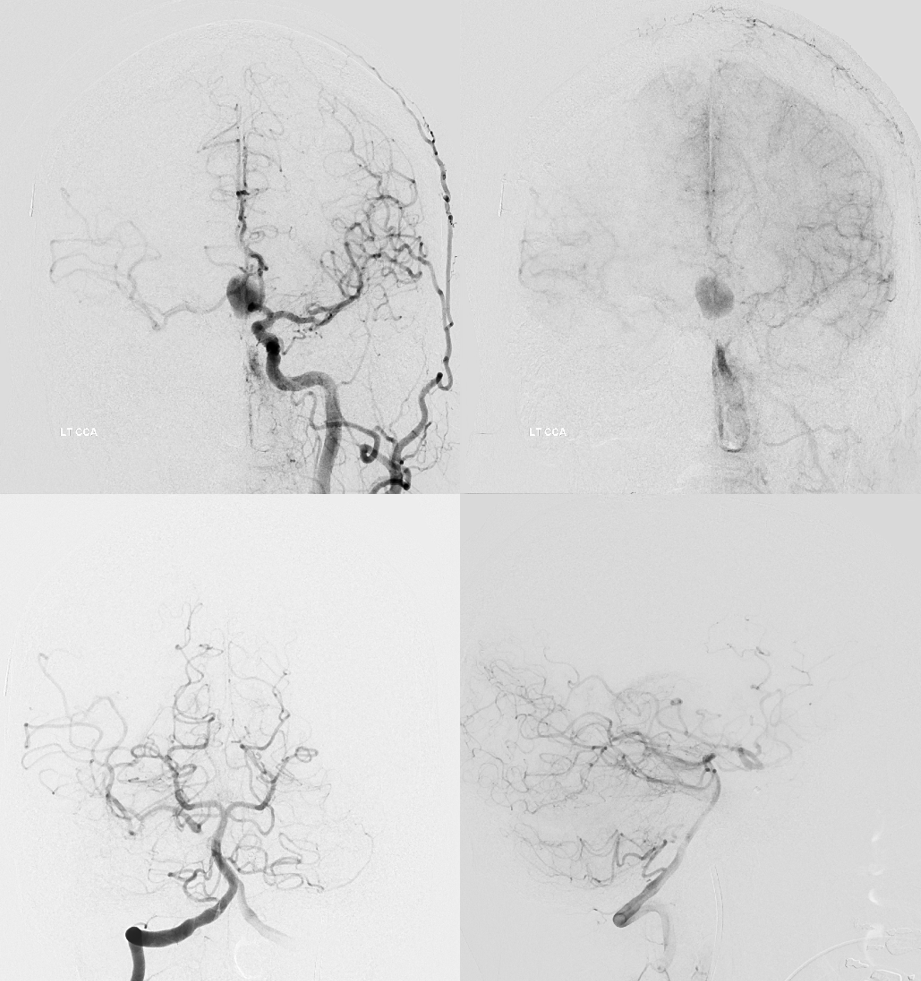

Now to the left side

Two Pipe Shields are placed. This is how we work. This big one is not a job for one and done

Post. Bilateral injections. The right ACA is supplied retrogradely via the ACA-ACA bypass. The MOST important finding here is that there is no longer flow across the ACOM. This is what flow modification is. Changing dynamics to impact aneurysm.

Robust bypass supports superior division and some more

No aneurysm, as suspected

Stereo pairs

Bypasses. Note A3-A3 patent bypass, as well as STA-MCA. Both seen thru radiolucent skull windows